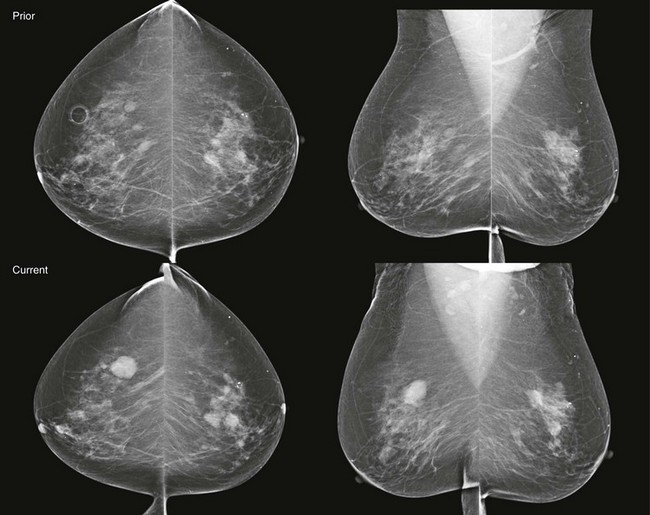

CASE 8-6. A screening mammogram on an 80-year-old woman is compared with a previous mammogram from 1 year ago. The patient has a history of multiple bilateral cysts diagnosed by US and core biopsy of a left breast mass revealing fibroadenoma. Can the rule of multiplicity be applied?

CASE 8-6. There are multiple bilateral masses. However, the findings cannot be considered benign because one mass, in the upper-outer quadrant of the right breast (arrows), has enlarged markedly since the previous mammogram and, therefore, warrants diagnostic evaluation. US shows an oval, circumscribed, solid mass with parallel orientation in the 10 o’clock position. Biopsy is indicated because of the rapid enlargement of the mass. Core biopsy revealed benign phyllodes tumor associated with lobular carcinoma in situ with the same diagnosis at excision.